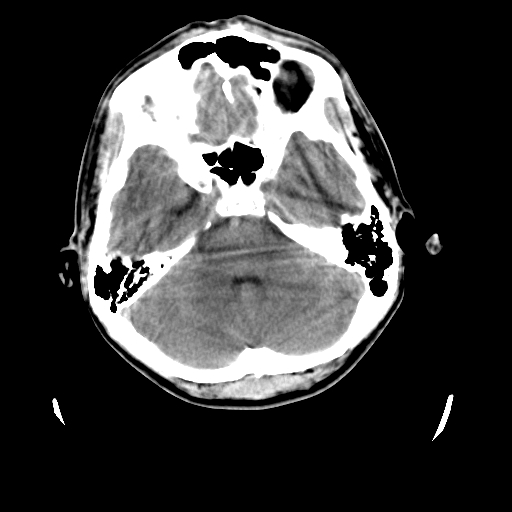

标题: CT23601:男, 17岁,剧烈头痛一小时。 [打印本页]

男, 17岁,剧烈头痛一小时。

颅脑ct轴位平扫颅内未见明确异常;建议:必要时复查。

颅脑ct平扫颅内未见明确异常;剧烈头痛,建议必要时dsa造影。